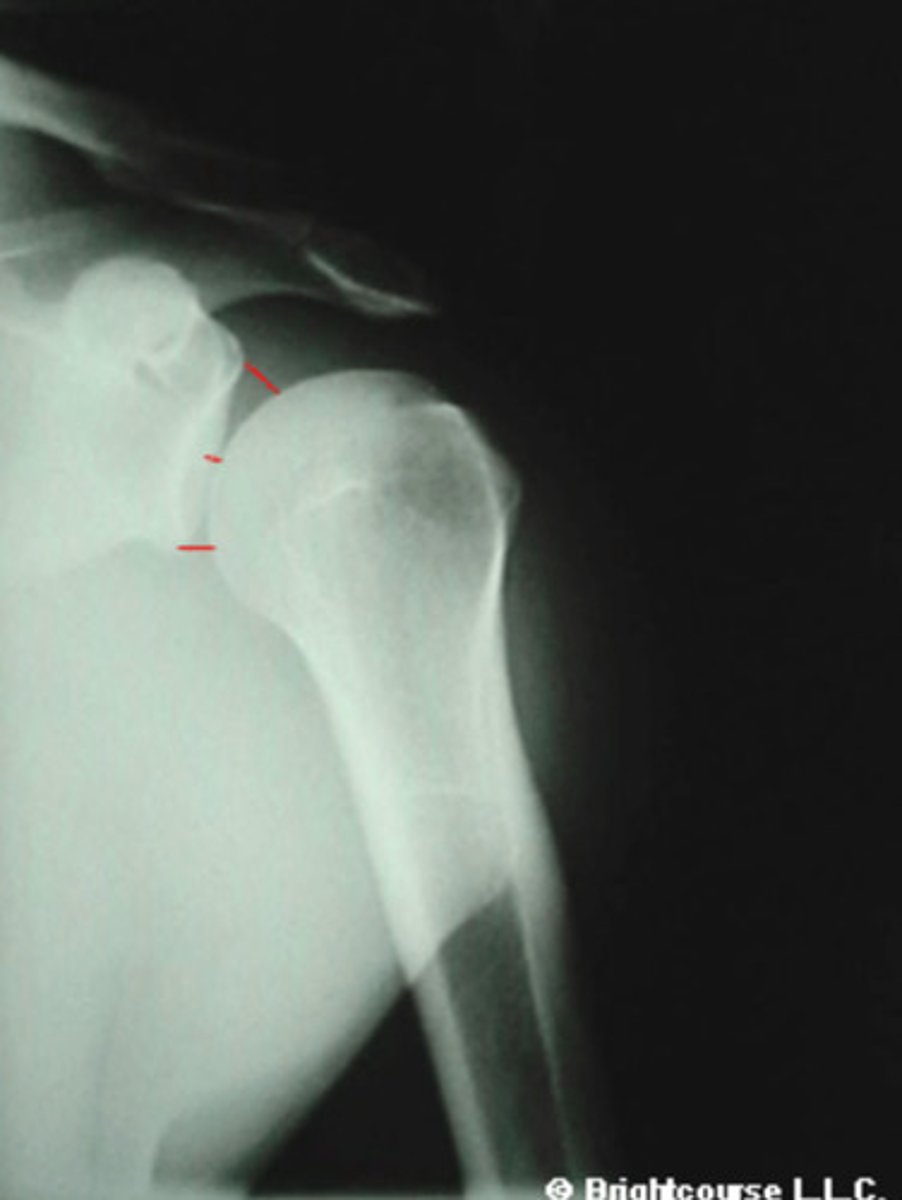

AC joint space

What space is being indicated in this image?

2-4mm

What is the normal measurement for the AC joint space?

Acromiohumeral joint space

What is being indicated by the number 2?

7-11 mm

What is the normal measurement for the Acromiohumeral joint space?

4-5 mm

What is the normal measurement for the Glenohumeral joint space?

AP External Rotation of Shoulder

What radiographic projection is the Acromiohumeral joint assessed upon?